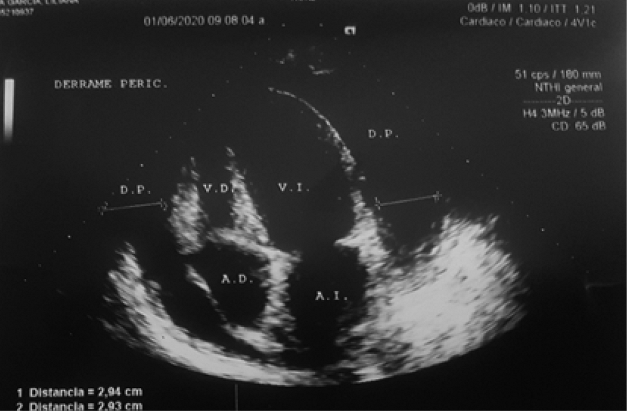

Ecocardiografía bidimensional y Doppler (01/06/2020): función diastólica de ventrículo izquierdo normal, insuficiencia mitral y tricuspídea leve, signos indirectos de hipertensión pulmonar y signos sugerentes de taponamiento cardiaco. Ver figura 3.

Ecocardiograma post pericardiocentesis (02/06/2020): Hipertensión pulmonar leve a moderada con repercusión hemodinámica, derrame pericárdico leve sin repercusión hemodinámica. Ver figura 4.